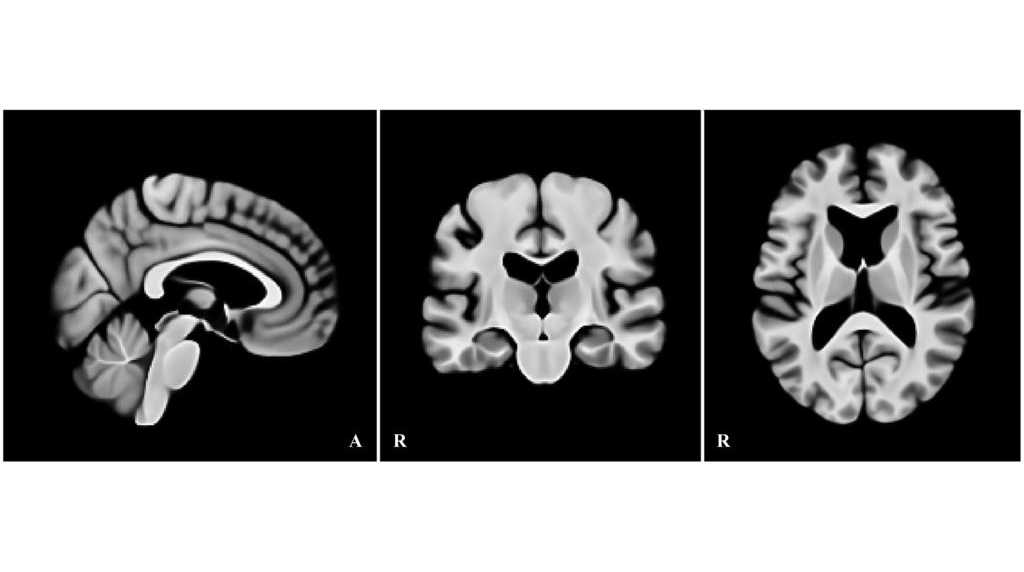

本研究では、加齢に伴う形態変化――特に拡大した側脳室や皮質の萎縮――を前提に、高齢者の脳画像を適切に基準化できる高齢者向け標準脳テンプレートを作成しました。2020年国勢調査に基づく日本の高齢者の男女比と年齢分布を考慮し、標準脳の構成が実情を反映するよう設計しています。作成データとしてOASIS-1の高齢者90例、検証データにはIXIの282例を用い、従来広く用いられているMNI152と比較しました。

前処理ではバイアス補正(N4)、強度正規化、頭蓋外除去を行って、各画像データの条件を統一しました。整合(登録)は段階的に実施し、まず剛体変換(6自由度)とアフィン変換(12自由度)で大域的な位置・形の差を補正したのち、ANTs(SyN) による非線形変換で微細整合を行いました。CC・MSE・SSIMの収束を確認しつつテンプレートを構築し、最終解像度は1mm等方としました。

検証では、IXIの各画像データを上記の手順で作成した高齢者向けテンプレートとMNI152の双方に同条件で登録し、全脳の整合(CC/MSE)と皮質下の領域(尾状核・海馬・視床・扁桃体)の一致度(Dice係数)を評価しました。その結果、60歳以降で整合が明確に向上し、CCは上昇、MSEは低下しました。特に、拡大した側脳室の位置合わせが安定し、加齢に伴う形態をより正しく反映できることが示されました。さらに、皮質下の各領域ではDice係数が1~4%向上し、局所の位置合わせ精度も改善しました。